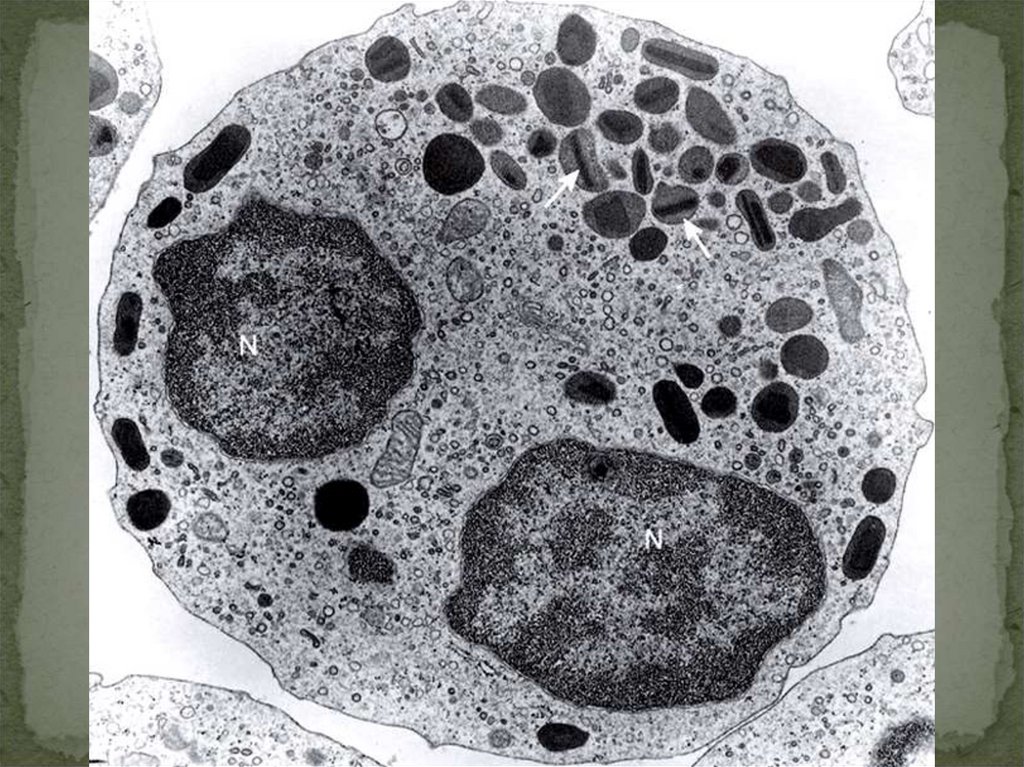

29.

30.

31. ОСНОВНЫЕ ФУНКЦИИ ЛИМФОЦИТОВ

В-ЛИМФОЦИТЫ – СИНТЕЗИРУЮТ АНТИТЕЛА

Т-ЛИМФОЦИТЫ –РЕГУЛИРУЮТ ИММУНИТЕТ

Т-КИЛЛЕРЫ, ЗАЩИТА ОТ ГЕНЕТИЧЕСКИ

ИЗМЕНЕННЫХ СОБСТВЕННЫХ КЛЕТОК

Т-СУПРЕССОРЫ – УГНЕТАЮТ ФУНКЦИИ

РАЗЛИЧНЫХ ЛИМФОЦИТОВ

Т-ХЕЛПЕРЫ – СПОСОБСТВУЮТ

ПРОЛИФЕРАЦИИ И ДИФФЕРЕНЦИРОВКЕ

ЛИМФОЦИТОВ (ЧЕРЕЗ ЦИТОКИНЫ)

О-НУЛЕВЫЕ (НАТУРАЛЬНЫ КИЛЛЕРЫ)

32.

ДИФФЕРЕНЦИРУЮТСЯ В МАКРОФАГИ